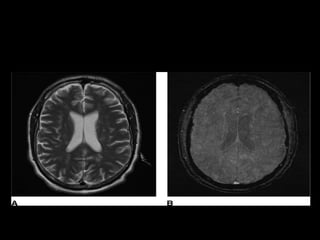

• MRI brain:

More sensitive

T2-weighted images typically demonstrate a

“starfield pattern” with multiple, small,

nonconfluent, hyperintense lesions.

The lesions occur in the periventricular,

subcortical, and deep white matter.